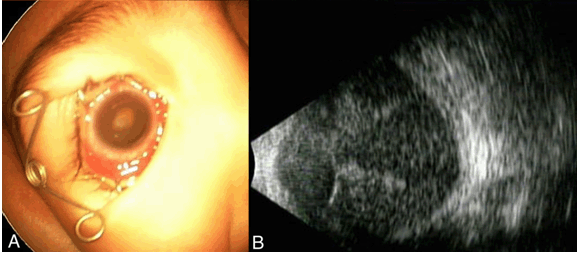

A healthy two-year-old boy presented with leukocoria of the right eye. On examination, the boy had poor visual fixation in the right eye and steady fixation in his left eye. His left eye decimal visual acuity was 0.4, and the right eye was light perception. Indirect ophthalmoscopy revealed a white tumor which resembled a retinoblastoma (Figure 1A). Ultrasonography showed a total retinal detachment and a lesion in the subretinal space with no calcification (Figure 1B). Computed tomography (CT) scan of head showed that the tumor was located in vitreous cavity of the right eye without calcification (Figure 1C). Whole body CT scan revealed no other tumors. We suspected a retinoblastoma and performed 2 cycles of chemotherapy consisting of vincristine, etoposide, and carboplatin (VEC). However, the VEC treatment had no effect, and the tumor grew rapidly (Figure 2A-B). The intraocular pressure (IOP) of the right eye increased to >60 mmHg. Finally, the vision in his right eye decreased to no light perception (NLP). The patient also lost his appetite due to the severe pain of right eye. Given the uncertainty over the clinical diagnosis, the poor visual prognosis, sever pain, and absolute glaucoma, the right eye was enucleated. His state was improved after the operation.

Figure 1: Fundus photograph, ultrasonographic B-scan image, and computed tomographic (CT) image of an eye with massive retinal gliosis. (A) Fundus photograph showing a white tumor resembling a retinoblastoma, (B) Ultrasonographic image (B-scan) showing a total retinal detachment and a lesion in the subretinal space with no calcification, and (C) Computed tomographic (CT) image of the head reveals the tumor in the vitreous cavity of the right eye without calcification.

Figure 2: Photograph of the anterior segment and ultrasonographic B-scan image of an eye with massive retinal gliosis. (A) Exterior photograph showing a white tumor in the posterior pole of the eye, (B) B-scan image showing mass in the vitreous cavity.